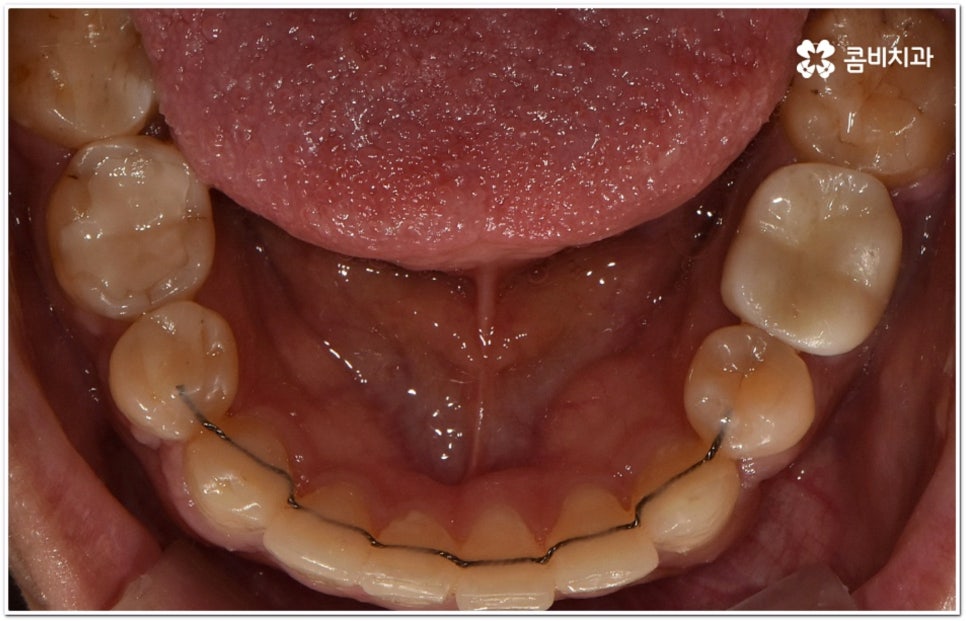

또한 구조적인 부분에 원인이 있었다면 교정 치료를 받은 후에도 원래대로 치열이 돌아가려고 하는 회귀 경향이 좀 더 강하게 일어날 수 있어요. 그렇기 때문에 치과에서 말씀드린 유지 장치를 잘 착용하면서 사후 관리를 철저하게 해 줘야 보다 오랜 시간 동안 바른 치열을 유지하면서 이를 건강하게 사용할 수 있습니다.

가철식(뺐다 꼈다 할 수 있는) 유지 장치는 눈에 잘 띄지 않고 식사를 할 때나 중요한 자리에서 잠깐씩 뺄 수 있다는 장점을 가지고 있지만 착용하는 시간이 부족하게 되면 혹여 치열이 다시 삐뚤어지거나 교합이 어긋나게 되어 심한 경우 재교정을 받아야 하는 상황까지도 이를 수 있기 때문에 교정이 끝난 초기에는 환자분들께서 주의를 기울여서 불가피한 경우가 아니라면 계속해서 착용을 해주시길 권고드리고 있어요. 그 이후에는 치료하신 치과의 안내에 따라 착용 시간을 줄여가면서 정기적인 검진을 받으시면서 관리를 해주시는 게 좋아요. 이에 반해 고정식 유지 장치는 착용 시간을 신경쓰지 않아도 되지만 부착시킨 철사로 인해 칫솔질이 어려워지고 치석이 잘 생기는 등 위생 문제가 발생할 수 있다는 점을 유의해야 하므로 주기적으로 검진을 받으면서 스케일링 치료를 통해 구강 내 위생 관리를 철저하게 해 주면 도움이 될 거예요. 가장 좋은 것은 고정식 유지장치와 가철식 유지장치를 둘 다 착용을 하시는 게 도움이 되므로, 치료를 담당하시는 원장님과 자세히 상담받아보시길 권장 드려요.